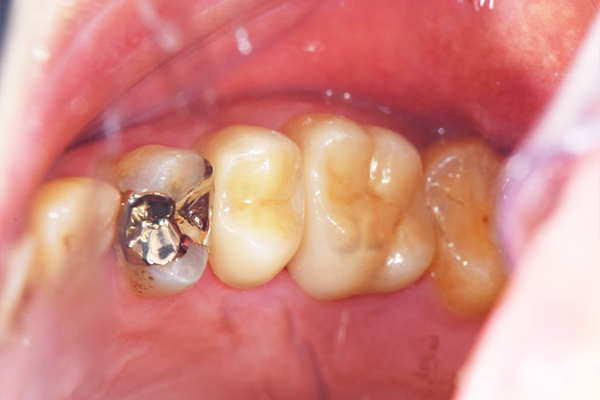

インレーの症例

現在の治療費と異なる場合がございます。最新の治療費は料金表をご確認ください。

インレー症例

治療前

途中経過

治療後

年齢・性別 43代・女性

主訴 パラジウムインレー2次カリエスの治療

治療内容 左上6セラミックインレー・

左上7ゴールドインレー

治療期間 10日程度

リスク・副作用 虫歯が深ければ、つけた後しみたり、痛みが出る可能性がある。 その場合は神経をとる処置をする。

歯ぎしり、くいしばりでセラミックインレーが割れることがある。

費用 セラミックインレー 55,000円

ゴールドインレー 88,000円